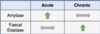

What are the investigations involved in appendicitis?

- bloods - which will show leucocytosis and elevated CRP